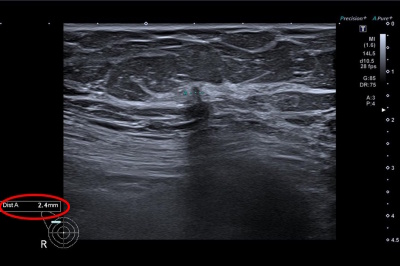

„Od ledna 2024 do srpna 2025 využilo možnost vyšetření s přispěním umělé inteligence 6397 našich klientek. Na základě nálezu pomocí AI absolvovalo 49 našich pojištěnek biopsii a u 34 z nich se potvrdil maligní nález. Využívání umělé inteligence nejen v rámci prevence tedy podle nás rozhodně dává smysl,“ říká MUDr. Jitka Vojtová, MBA, zdravotní ředitelka OZP.

Zvýšený zájem o vyšetření se zapojením umělé inteligence při prevenci rakoviny prsu dokládají statistiky loňského a letošního roku Mamodiagnostických center Waltrovka a Beroun. V roce 2024 o něj projevilo zájem 54 % pacientek (celkem 26 481, z toho s využitím AI 14 293), v roce 2025 už se jedná téměř o 74 % (dosud celkem 18 890, z toho AI 13 993). Špičková technologie se tak prakticky během jednoho roku v praxi stala standardem. Lékaři zároveň potvrzují zvýšení záchytu nádorů o zhruba 16,7 %, což odpovídá i výsledkům zahraničních studií.